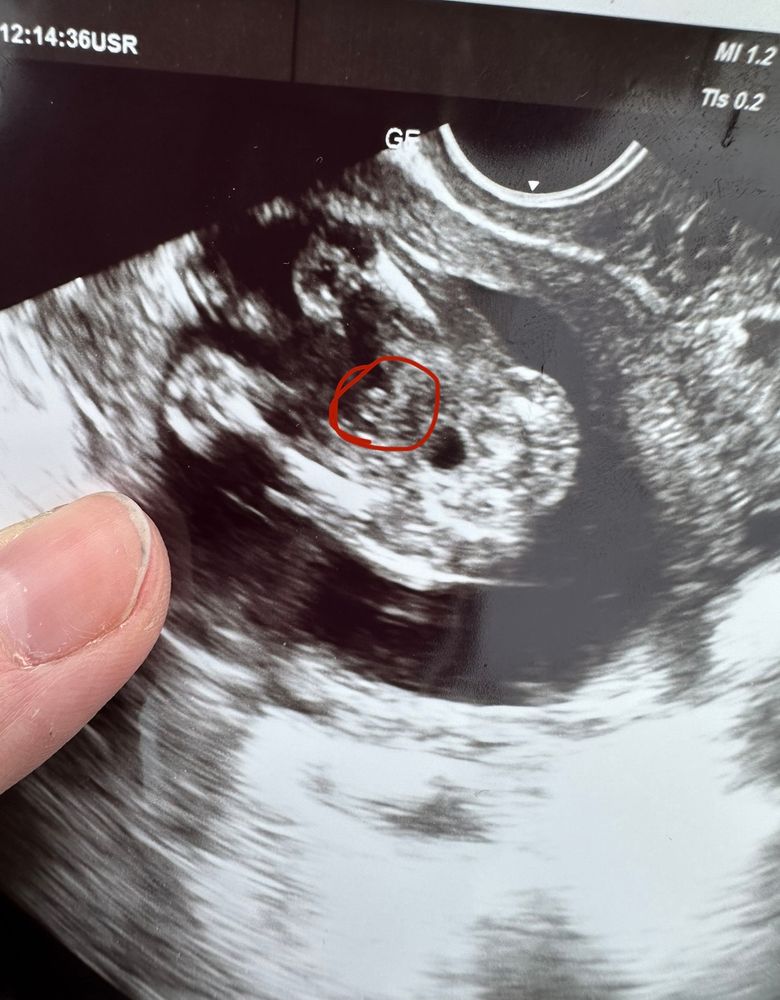

Изображение У нас тоже мальчик

barsilina, на фото 12 неделя , на 12 недели сказали

Ничего девчачьего, действительно на пацана похож. Я оба варианта видела

На девочку не похоже... У девочек вареничек прям видно😅